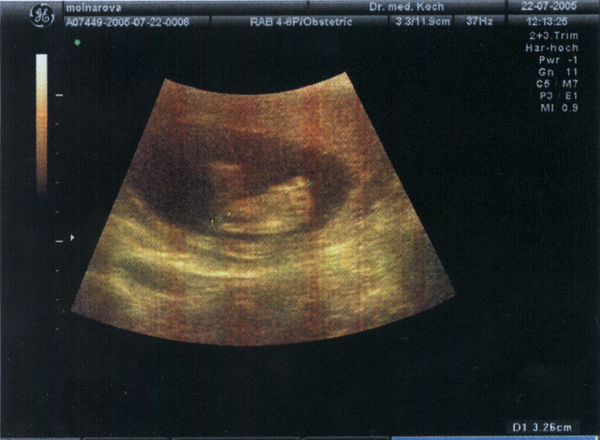

22.07.05 - 20. Woche - 22,0cm